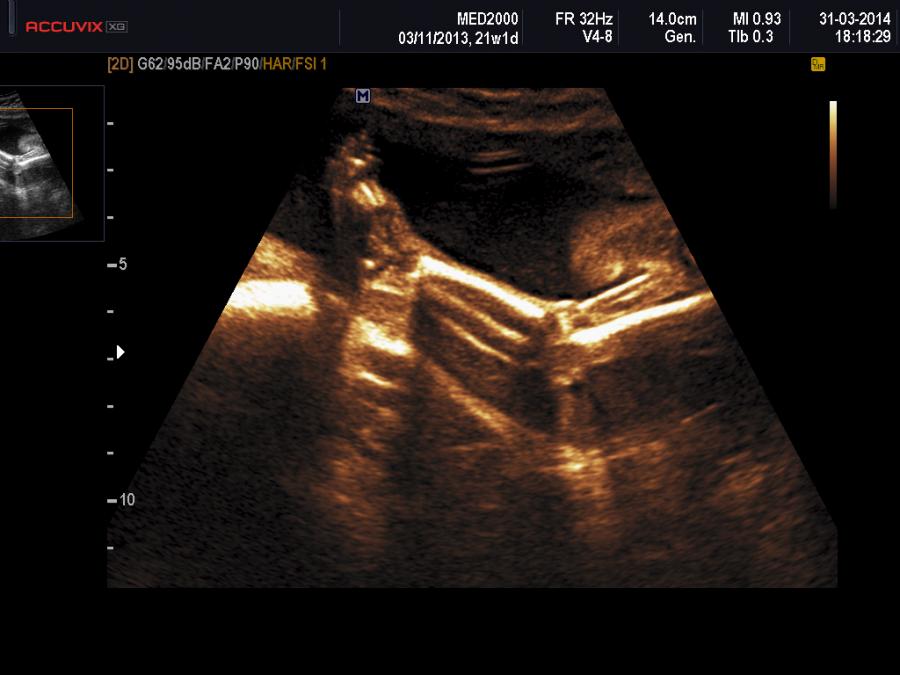

Con l'ecografia è possibile studiare i rapporti articolari tra tibia e femore confrontando le linee tangenti alla diafisi di queste due ossa lunghe. Come si può osservare dallo schema allegato nella sezione Foto, in basso, è possibile documentare l'allineamento o il mancato allineamento di tibia e femore per porre una diagnosi differenziale tra le tre varianti di CGR: iperestensione, sublussazione, dislocazione. Nell'iperestensione le superfici anteriori di tibia e femore sono allineate e le tangenti alle diafisi sono concordanti; nella sublussazione le tangenti alle diafisi di tibia e femore non sono concordanti per cui la tangente alla diafisi della tibia si continua con la superficie anteriore del femore; nella dislocazione le tangenti alle diafisi di tibia e femore non sono concordanti e la superficie posteriore della tibia si allinea con la superficie anteriore del femore.